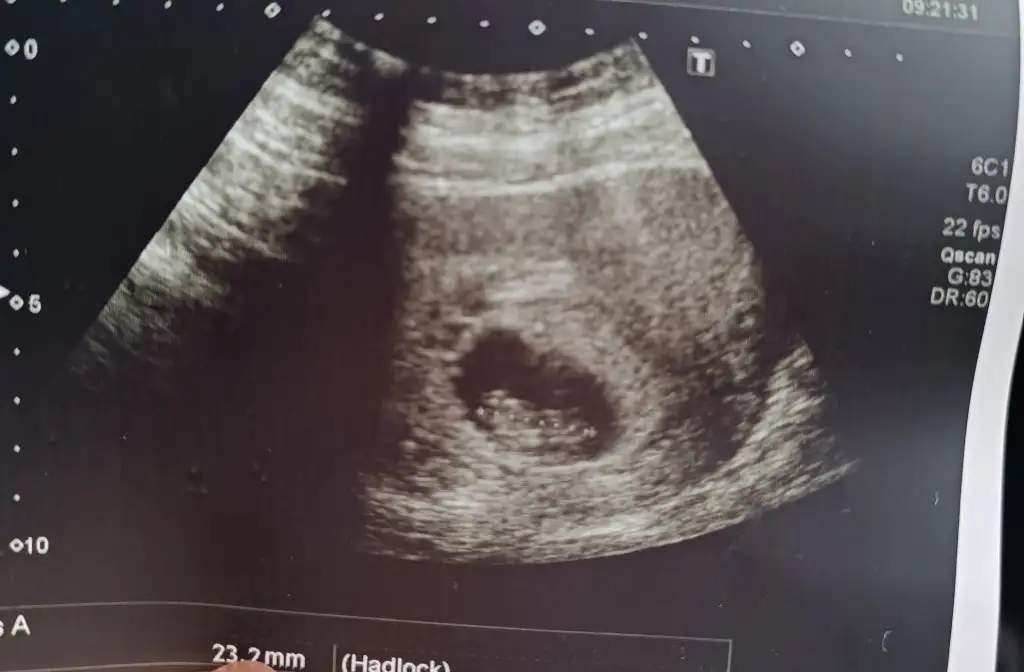

Bana da tahmin de bulunur musunuz 9 haftalıgiz

Direkt erkek diyorumBenim içinde tahmini olan var mı kızlar